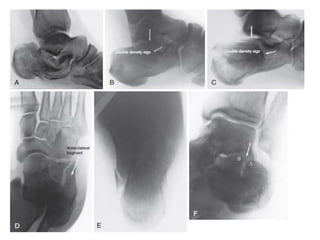

Estudios de imagen

• Angulo de Gissane 105º a 135º • Angulo de Bôhler 20º a 40º

Axial de calcáneo Harris

Proyeccion de

Broden

Coughlin, Mann . Pie y tobillo, Cap 38 Fracturas de calcaneo. Marban

Estudios de imagen •Angulo de Gissane 105º a 135º • Angulo de Bôhler 20º a 40º

Tomografía • Cortes 3-5 mm • Coronales : mejor carilla articular posterior, el sustentaculo, t peroneos, TFH • Axial : articulación calcaneo cuboidea . Prt anteroinferior carilla posterior y sustentáculo

Proyeccion de Broden Coughlin, Mann. Pie y tobillo, Cap 38 Fracturas de calcaneo. Marban